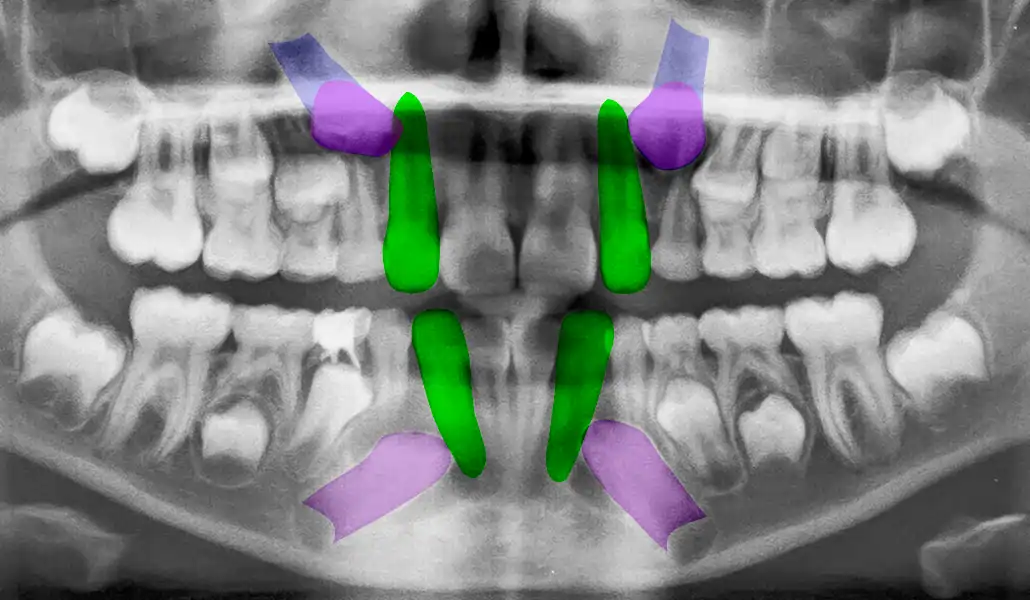

El tratamiento se organiza en etapas claramente definidas. Primero se realiza una evaluación clínica e imagenológica que permite entender la posición dentaria, la relación de mordida y las condiciones biológicas del paciente.

A partir de ese diagnóstico, se define si la ortodoncia está indicada y bajo qué condiciones debe realizarse. Antes de iniciar el tratamiento, se resuelven las patologías que puedan interferir, como caries o enfermedad periodontal.